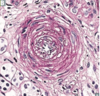

Thrombocytopenic Thrombotic purpura- hemolytic uremic syndrome (TTP-HUS)

1. Platelet activation

2. Diffuse microvascular thrombosis

3. Microangiopathic hemolyitc anemia with schistocytes

4. Thrombocytopenia

TTP is almost always characterized by a normal PTT (unlike in DIC)

Would present with platelt rich thrombi in the glomeruli and arterioles

Pt presentation has pentad:

fever, neurologic symptoms, renal failure, anemia, thrombocytopenia